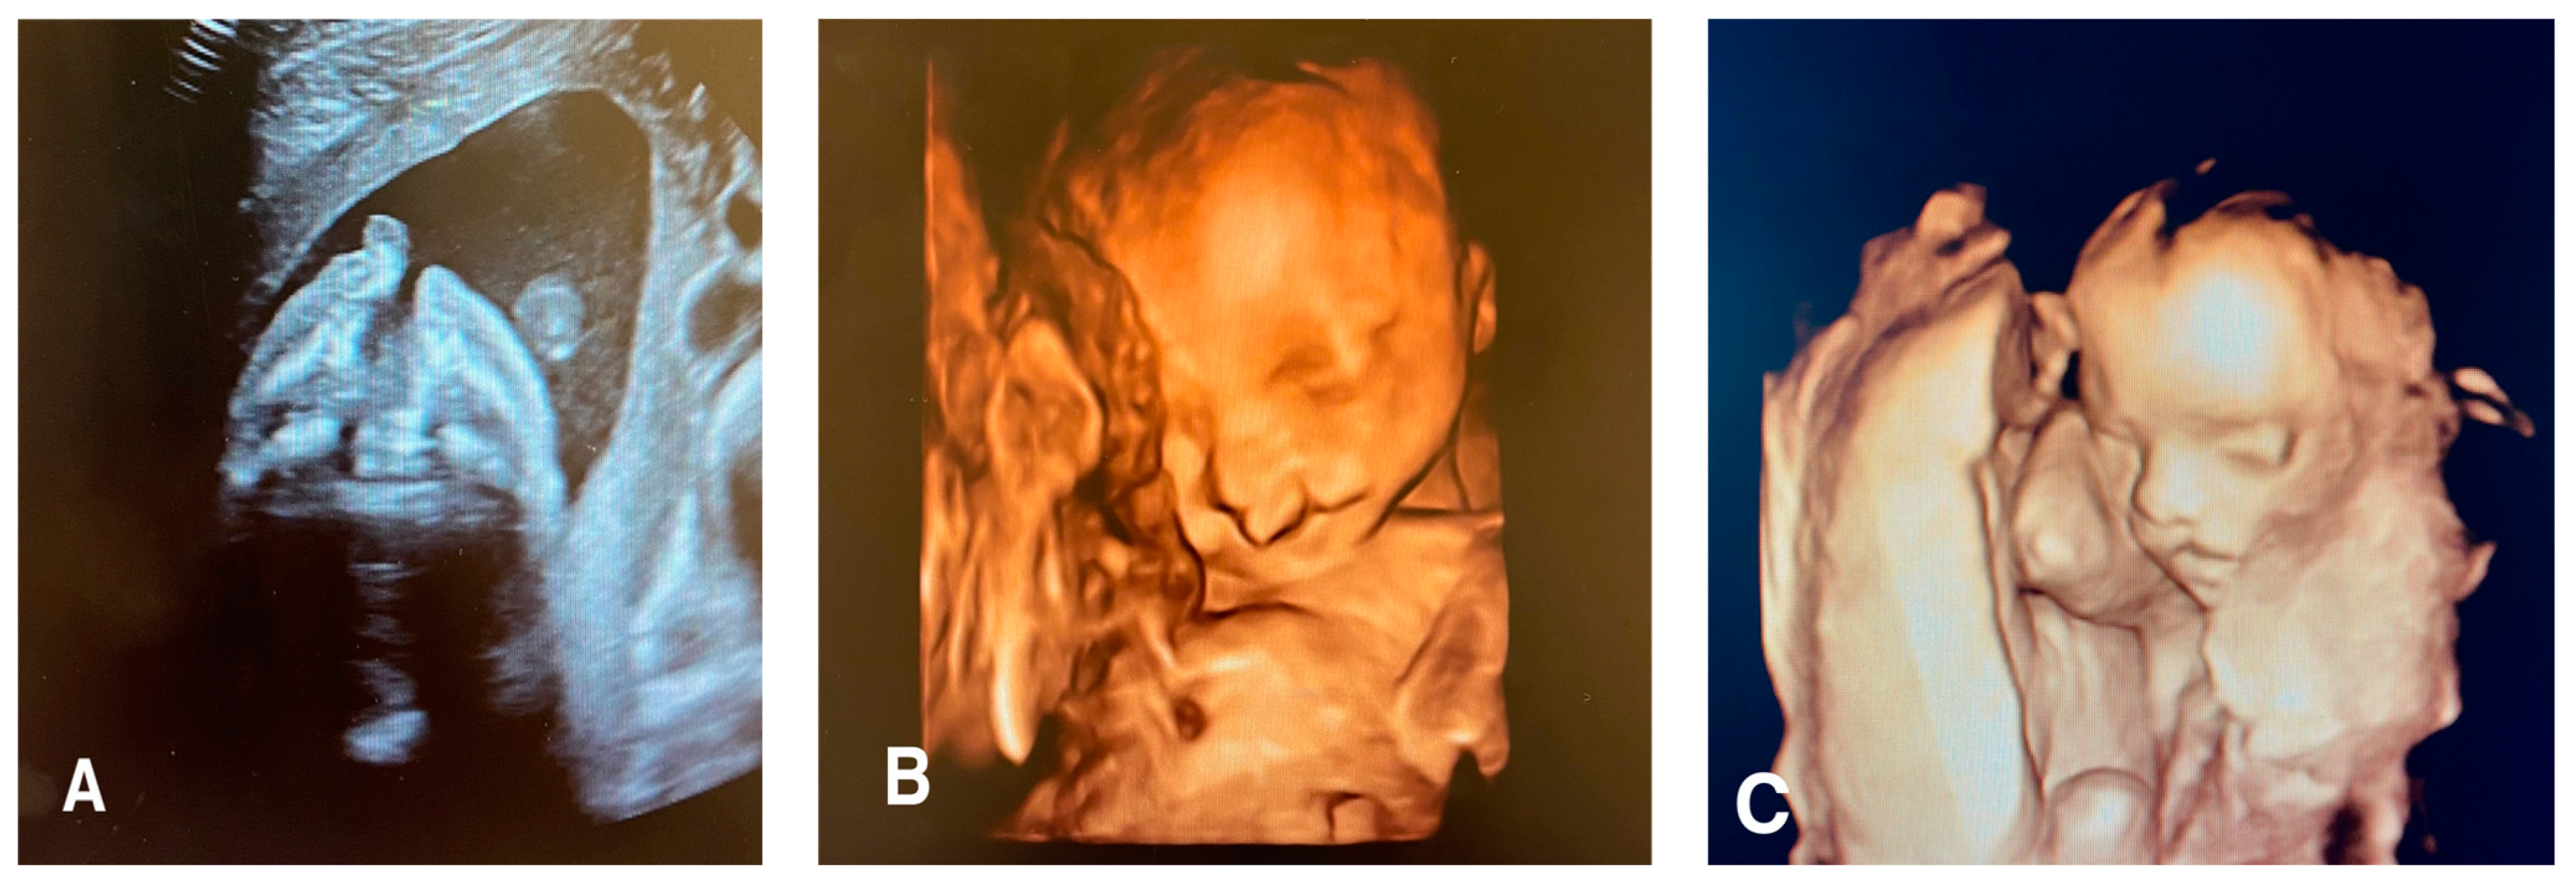

Facial clefts include a wide variety of pathologies that result from the failure of fusion in the facial area during the early embryonic/fetal period, leading to a gap in the fetal face [20]. These clefts can affect the lip, philtrum, alveolus, and hard and soft palate to varying degrees. Facial clefts may be typical or atypical (Figure 1).

Figure 1.

(A) Axial view of a 21 week old fetus with unilateral left cleft lip, cleft palate, and premaxillary protrusion (B) A 3D surface rendered image of the same fetus with unilateral left cleft lip and cleft palate. (C) A 3D surface rendered image of a 16 week old fetus with isolated left unilateral cleft lip.